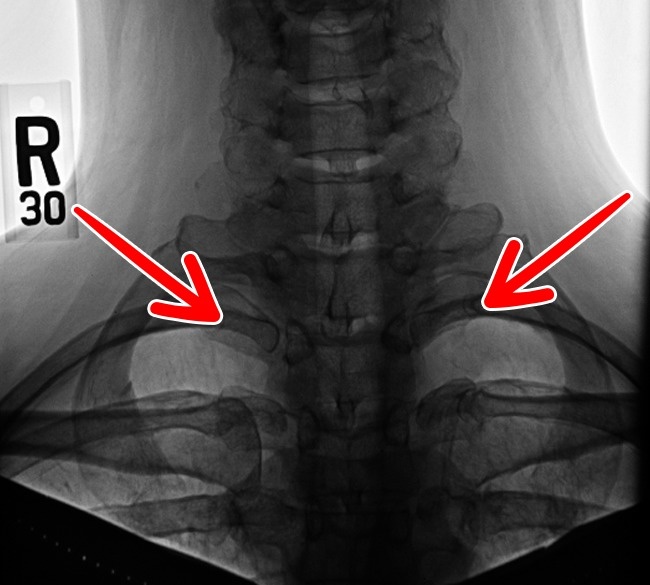

5. Neck rib

A set of cervical ribs, possibly a leftover from the age of reptiles, still appears in less than 1% of the population. Some people have it only on their left or right side, while some have both. They often cause nerve and artery problems.